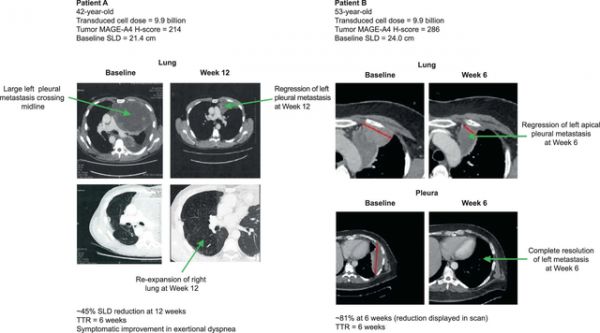

SPEARHEAD-1的I期临床试验中,有2例滑膜肉瘤患者在TCR-T细胞疗法Afami-cel治疗6周后均实现部分缓解(PR),肿瘤病变分别缩小了45%和81%。

截图来源于参考资料3,侵权请联系删除